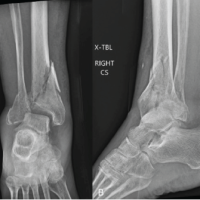

A 34-year-old male was brought to our emergency department following a high-energy road traffic accident. The patient’s complaints included severe pain, swelling, and an inability to bear weight on his left lower limb. Upon clinical examination, the left thigh had considerable soft tissue swelling and localised tenderness. Despite having stable vital signs, he appeared distressed due to the pain and swelling. X-rays of the left thigh revealed a triple-segmental shaft femur fracture (Fig. 1). This is an uncommon pattern–the femur is divided into five segments. Additional imaging revealed a bimalleolar fracture, a comminuted cuboid fracture, an undisplaced acetabulum fracture, and an undisplaced patella fracture (Fig. 2).